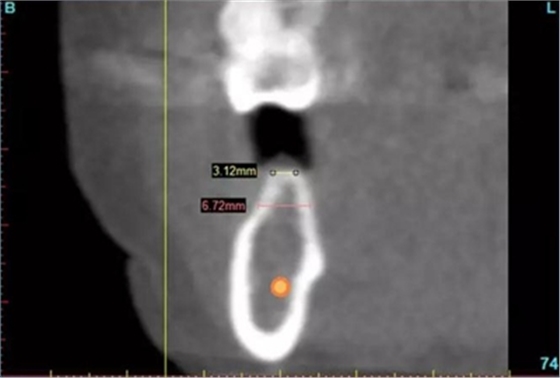

圖3a.右下第一磨牙無(wú)牙區(qū)位點(diǎn)術(shù)前和骨增量術(shù)后CBCT掃描。術(shù)前掃描顯示牙槽嵴頂水平骨寬度3.1mm

圖3b. 術(shù)后5個(gè)月,在無(wú)牙牙槽嵴的不同水平上達(dá)到2-5mm 的水平骨增量